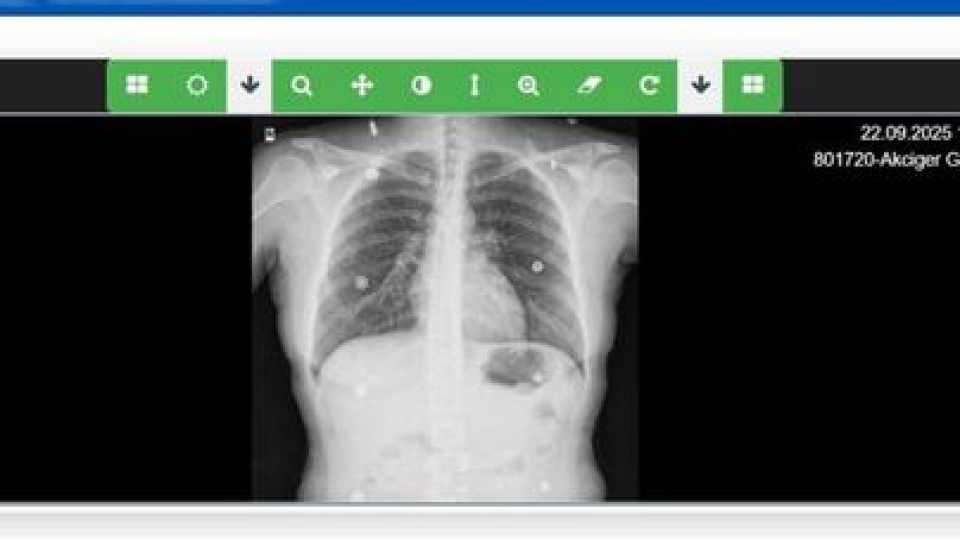

Sağlık Bilgi Sistemleri Genel Müdürü Özgür Sezer, 4-10 Ocak Verem Eğitim ve Farkındalık Haftası nedeniyle yaptığı açıklamada, Bakanlığın 'Akciğer Görüntüleme Sistemi'ni hayata geçirdiğini belirtti.

Genel Müdür Sezer, sistem ile öncelikli amacın tüberkülozun tanı, izlem ve raporlama süreçlerinin dijital ortamda desteklenmesi olduğunu kaydederek, "Sistem, tüberküloz hastalığının düzenli takibini kolaylaştırıyor ve hasta yönetim süreçlerini hızlandırıyor. Akciğer Görüntüleme Sistemi, Teleradyoloji Sistemi ile entegre çalışıyor, bu sayede dispanserlerde çekilen görüntüler e-Nabız üzerinden hastalar ve hekimler tarafından kolaylıkla görüntülenebiliyor" dedi.

171 verem savaş dispanserini bu sisteme entegre ettiklerini belirten Genel Müdür Sezer, "Projenin hayata geçirildiği günden bu yana yaklaşık 8 bin akciğer grafisi sisteme kaydedildi. Ülke genelindeki dispanserlerimizde elde edilen akciğer görüntülerini tek bir ulusal altyapı üzerinde topluyor, güvenli biçimde arşivliyoruz. Bu görüntüler gerektiğinde hekimlerimiz tarafından uzaktan değerlendirilebiliyor. Böylece hem tanı süreçlerinde standartlaşmayı sağlıyoruz hem de hastalık verilerini bölgesel ve ulusal ölçekte anlık olarak izleyebiliyoruz. Yeni kurduğumuz sistemle; görüntülerin tüm merkezlerden erişilebilir hale getirilmesi ile tanı ve tedavi süreçlerini hızlandırdık ve süreçlerin dijital hale getirilmesi sayesinde çok önemli kazanımlar elde ettik" ifadelerini kullandı.